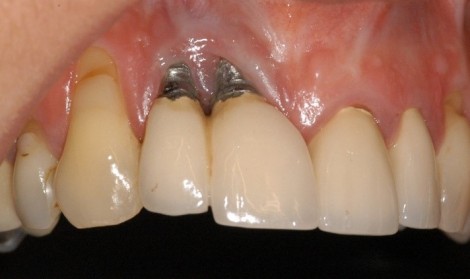

علت استفاده نشدن ایمپلنت دندان می‌تواند مربوط به واکنش های حساسیت به فلز تیتانیوم که در پایه ایمپلنت است باشد.

این نوع از واکنش حساسیت های پوستی، اگزما، تورم، کهیر و تحلیل استخوان به‌ دلیل کاشت ایمپلنت دندان دیده شده است.

-وجود عفونت و التهاب در قسمتی از بافت لثه اطراف ایمپلنت